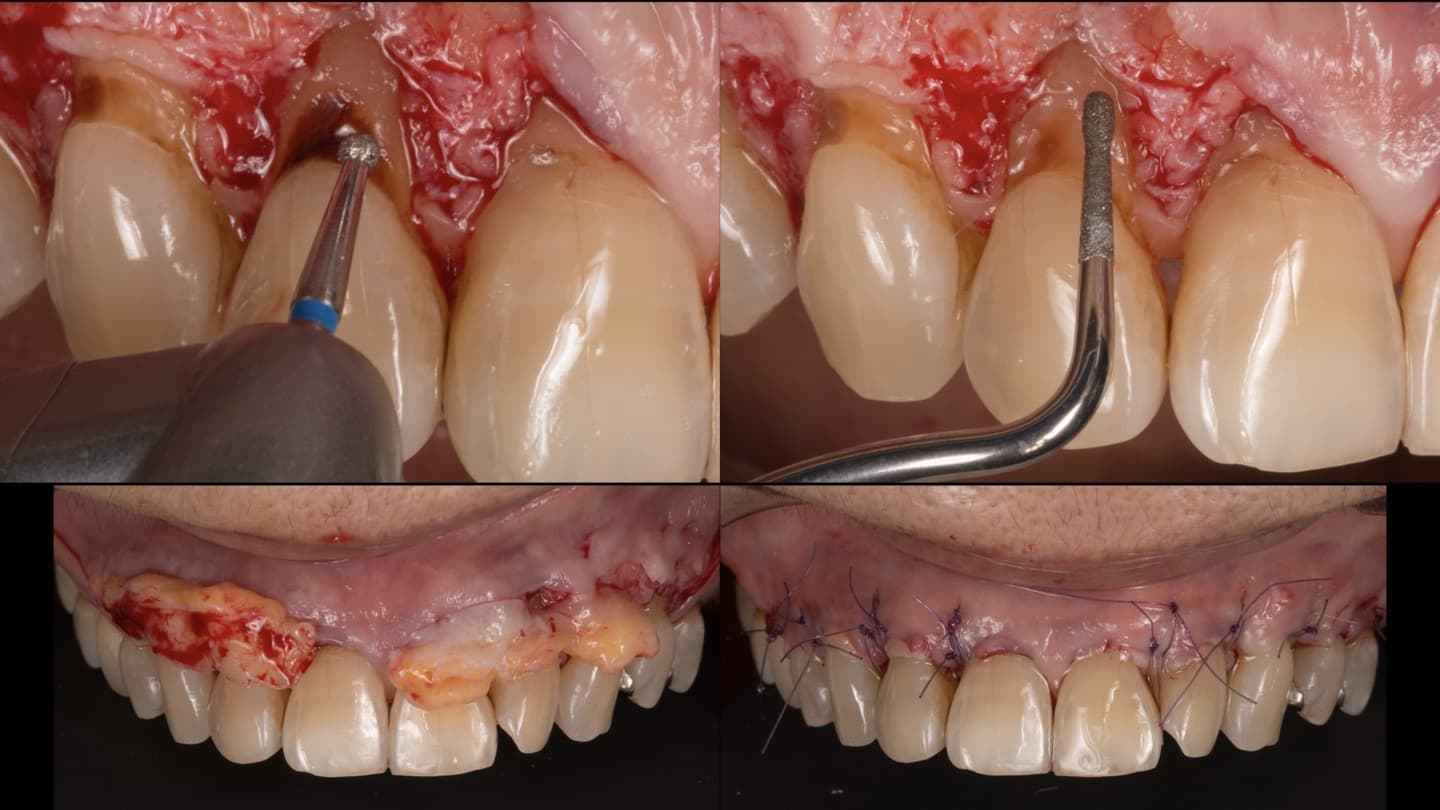

出来る限り歯を抜かない

一般的な歯周病(慢性歯周炎)に関する治療法は、ほぼ確立されています。私達は、出来る限り歯を抜かずに歯周病治療する事で歯を温存できるよう日々努力しています。

適切な治療を行えば、健康な口腔内を実現できます